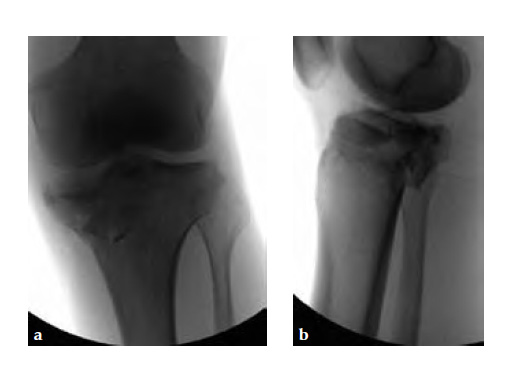

A 33-year-old male was involved in an altercation and suffered a gun shoot wound to his knee

Case provided by Brent Norris, Tulsa, USA.

Initially taken for incision and drainage and then ORIF . Patient placed in a floppy lateral position with the effected lower extremity externally rotated (opposite hip and shoulder bumped up about 3040) allowing exposure of the posterior medial knee. A posterior medial and an anteromedial incision were used to repair the fracture with a 67 cm skin bridge.

Postoperative healing was uneventful and the patient had no complications.